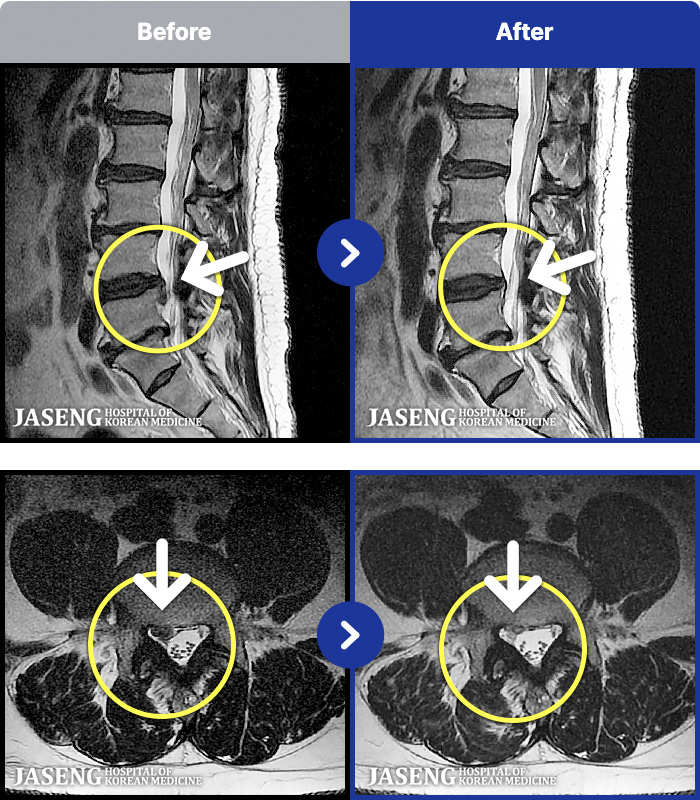

54 MRI ũ ʸ Ȯϼ.